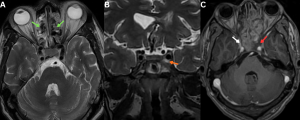

Fig 6: Clinical history:

A 50-year-old diabetic male presented with severe retro-orbital pain, ptosis, and cranial nerve palsies.

Figure A:

Axial T2-weighted MRI image demonstrates mucosal thickening within the bilateral ethmoid air cells (green arrows).

Figure B:

Coronal T2-weighted MRI image demonstrates T2 hyperintense soft tissue within the left cavernous sinus (orange arrow).

Figure C:

Axial post-contrast T1-weighted MRI image demonstrates absent contrast opacification of the left cavernous sinus (red arrow), consistent with cavernous sinus thrombosis. The right cavernous sinus shows normal contrast opacification (white arrow).